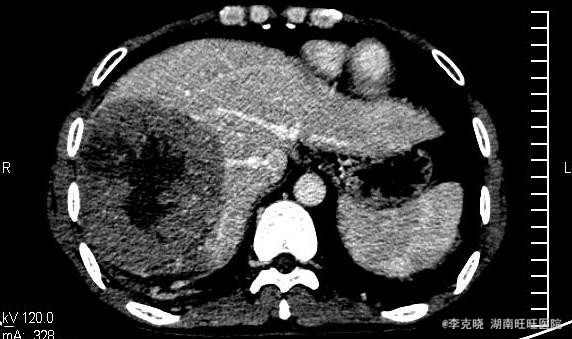

四测正常,皮肤巩膜无黄染,心肺部听诊未闻及杂音。腹平坦,未见胃肠型及蠕动波,无腹壁静脉曲张,全腹柔软,右侧肋缘深压痛,无反跳痛,肝肾无叩痛,肝肺浊音界清晰,肠鸣音正常。四肢活动自如,无水肿。 辅助检查提示:血常规、凝血常规基本正常,谷丙转氨酶278u/l,谷草转氨酶326u/l,AFP大于20000。上腹部CT增强提示:右肝巨大占位,平扫期呈低密度,动脉扫描时强化明显,静脉延迟象呈现低密度,结合病史考虑原发性肝癌可能,建议结合临床。

诊断:原发性肝癌(右肝巨块型)。治疗:考虑到患者的经济状况,结合肿瘤的影像学特点,经与患者充分沟通“以手术治疗为主的肝癌综合治疗思路”,最终患者选择先行TACE治疗。治疗后住院9天复查肝功能,转氨酶有下降趋势时,给予患者出院。一个半月后返院复查,转氨酶稍高,肿瘤内部碘油沉积满意,未见新生血管生成和新生病灶,建议患者继续观察、随访。

随访四个月,患者在第三个月时,碘油流空较多,予以加做一次TACE,碘油再次沉积良好,目前仍在随访当中。 我国是乙肝人口大国,乙肝、肝硬化、肝癌成为肝癌三步曲。无症状的乙肝病毒携带者、肝功能正常的慢性乙型、丙型肝炎,均应重视起来,不能因暂时没有症状、或者肝功能正常而不加以干预,乙肝患者一定注意DNA定量检测,若拷贝较高,建议口服抗病毒药物,如恩替卡韦,丙肝患者需定期查肝功能和影像学诊断,必要时应用干扰素等治疗,防止肝功能缓慢破坏。 肝癌的治疗从手术到多种手段的综合运用,尤其是当今手术已不存在禁区,然而中位生存时间、预后、五年生存率等20年来几乎无明显延迟。我们医务工作者是否应该认识到,对抗性的治疗是否有利于恶性疾病的治疗,扶正祛邪的祖国中医理论是否有可取之处?带瘤生存、与瘤共生和平相处是不是更由于创伤巨大的手术呢。此患者最终选择TACE,笔者认为十分赞同,经过四个月的治疗来看,肿瘤得到了有效遏制,生子速度大大延缓,而患者自身生活质量也比手术切除要高的多。